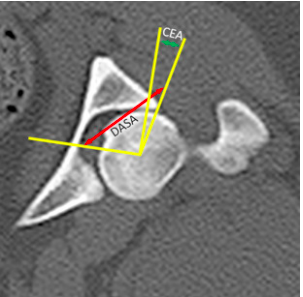

In the picture below two angles are depicted to measure hip laxity on CT images.

a. What do these abbreviations stand for and explain how the lines are drawn.

b. Do they correlate with the PennHIP outcomes?

a CEA = center edge angle

DASA = dorsal acetabular sector angle

The DASA angle is the angle between a line from the center of the femoral head to

the dorsolateral edge of the acetabular rim and the horizontal pelvic axis.

The CEA is measured between a line from the center of the femoral head to the

dorsolateral edge of the acetabular rim and a line perpendicular to the horizontal pelvic

axis.

b Yes they do correlate with the PennHIP distraction index and cartilage microdamage

at 30 months of age.